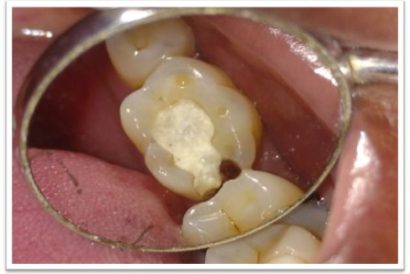

Patient Name:Akshay Gharat

Tooth Involved :16

Diagnosis :Caries Involving Enamel And Dentin Mesiocclusally

Treatment :Class Two Direct Composite Restoration Using Nanohybrid Composite

Before

After